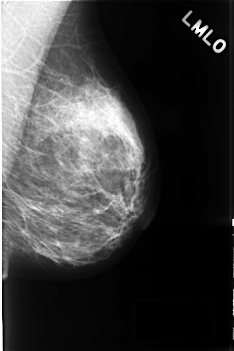

C_0437_1.LEFT_MLO

LEFT_MLO LINES 4560 PIXELS_PER_LINE 3032 BITS_PER_PIXEL 12 RESOLUTION 50 NON_OVERLAY